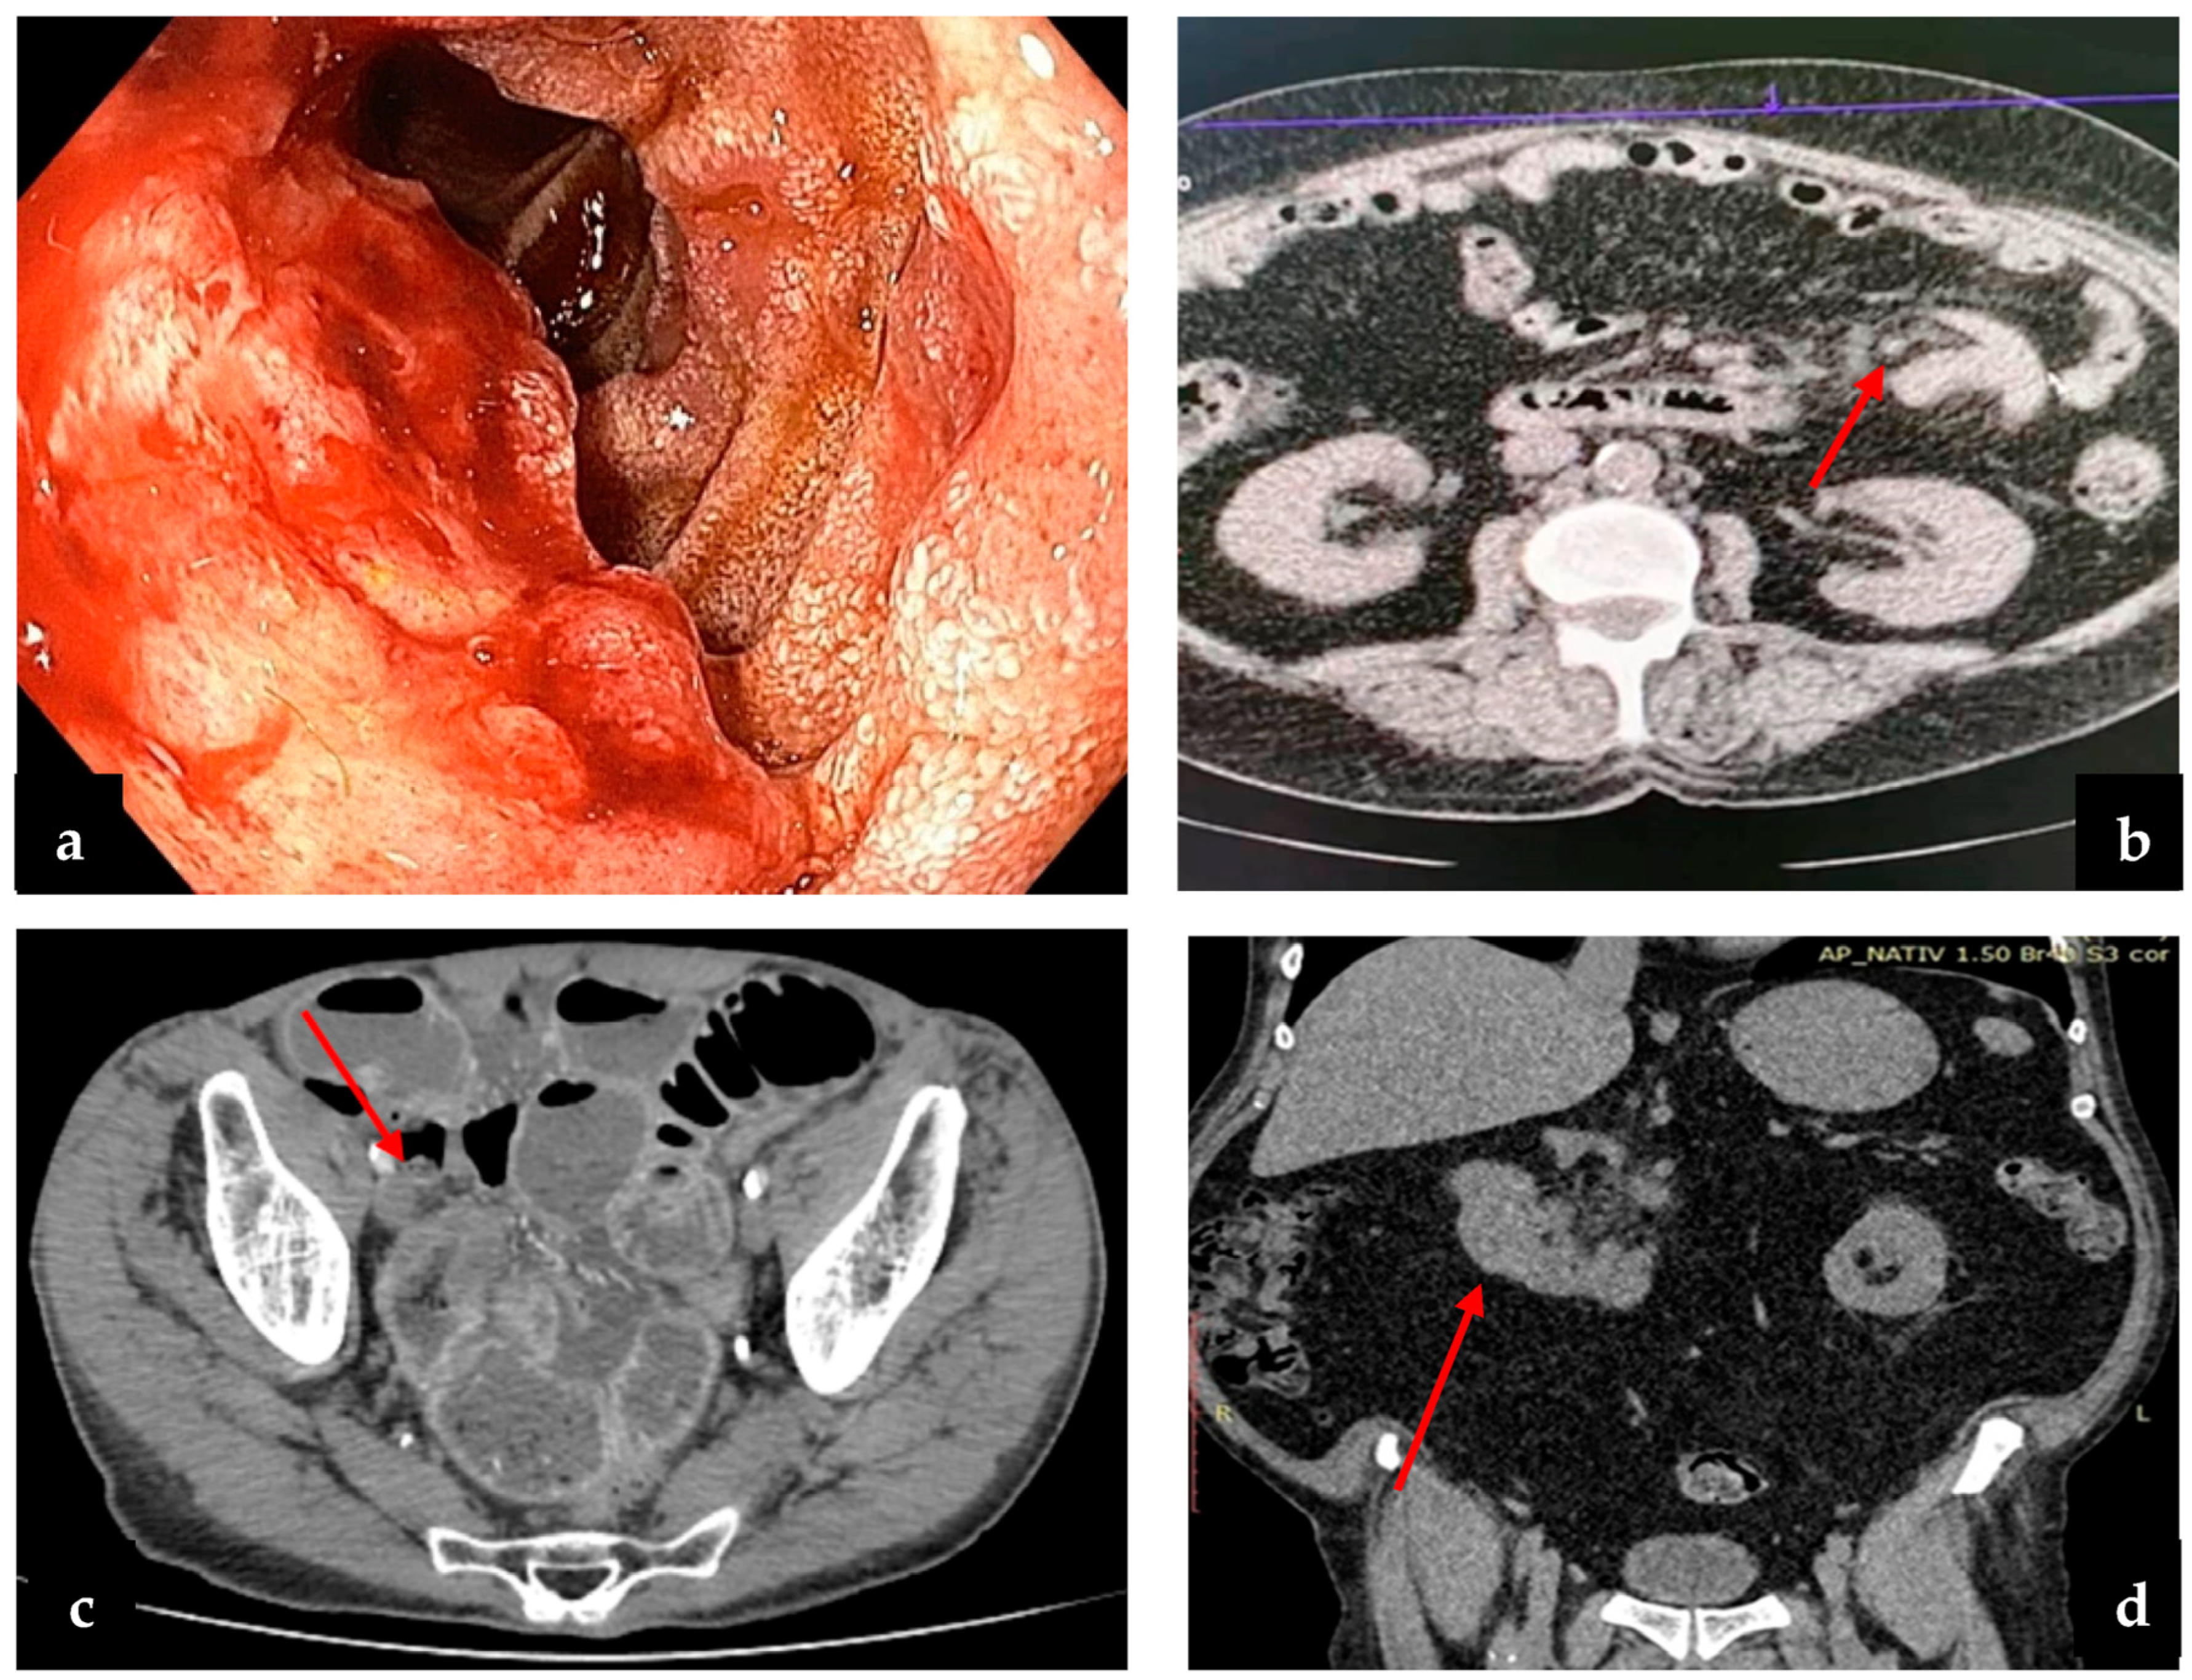

Figure 4.

(a) Endoscopic examination of a duodenal tumor; (b) CT exam of tumor bowel intussusception; (c) postcontrast CT scan, arterial phase, axial plane—there is a marked stenosing circumferential parietal thickening of a pelvic small bowel loop (arrow); (d) CT exam of duodenal tumor and perilesional lymph nodes.